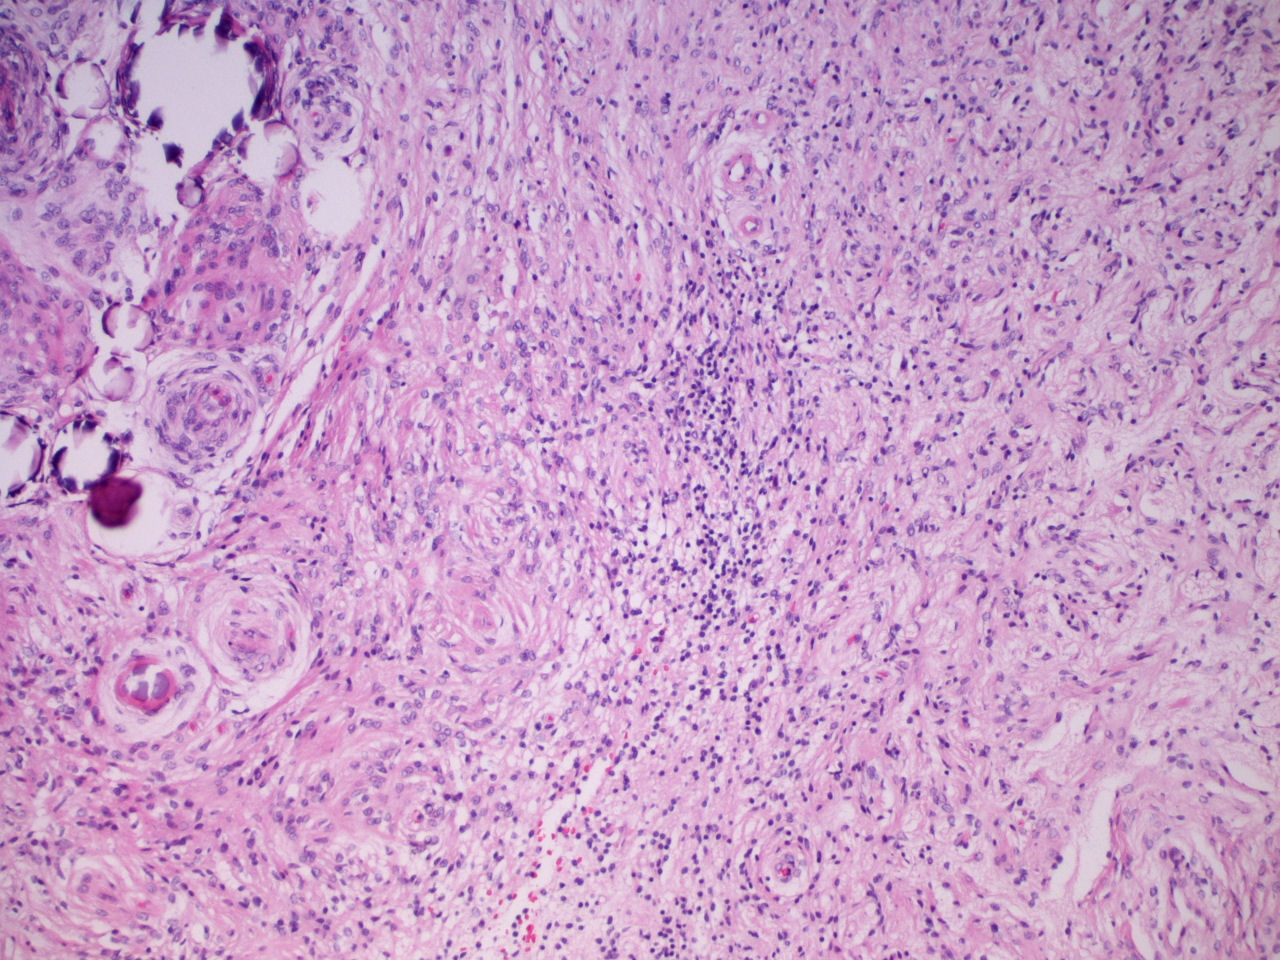

RM: Tumor localizado en valle silviano ¿intra- extraaxial? de 34 x 25 mm.. La lesión se rodea de mínimo edema y no presenta efecto masa significativo. (Figs. 1-2)

Fig. 1. Corte axial T2 mostrando lesión hiperintensa en valle silviano. ¿intra-extraaxial? Fig. 2. Corte axial T1 con contraste, captación intensa.

Fig. 3. Meningioma transicional sin atipias, mitosis o necrosis. H-Ex200 Fig. 4. Transición entre el meningioma superficial y la meningioangiomatosis en la corteza cerebral adyacente. H-Ex100